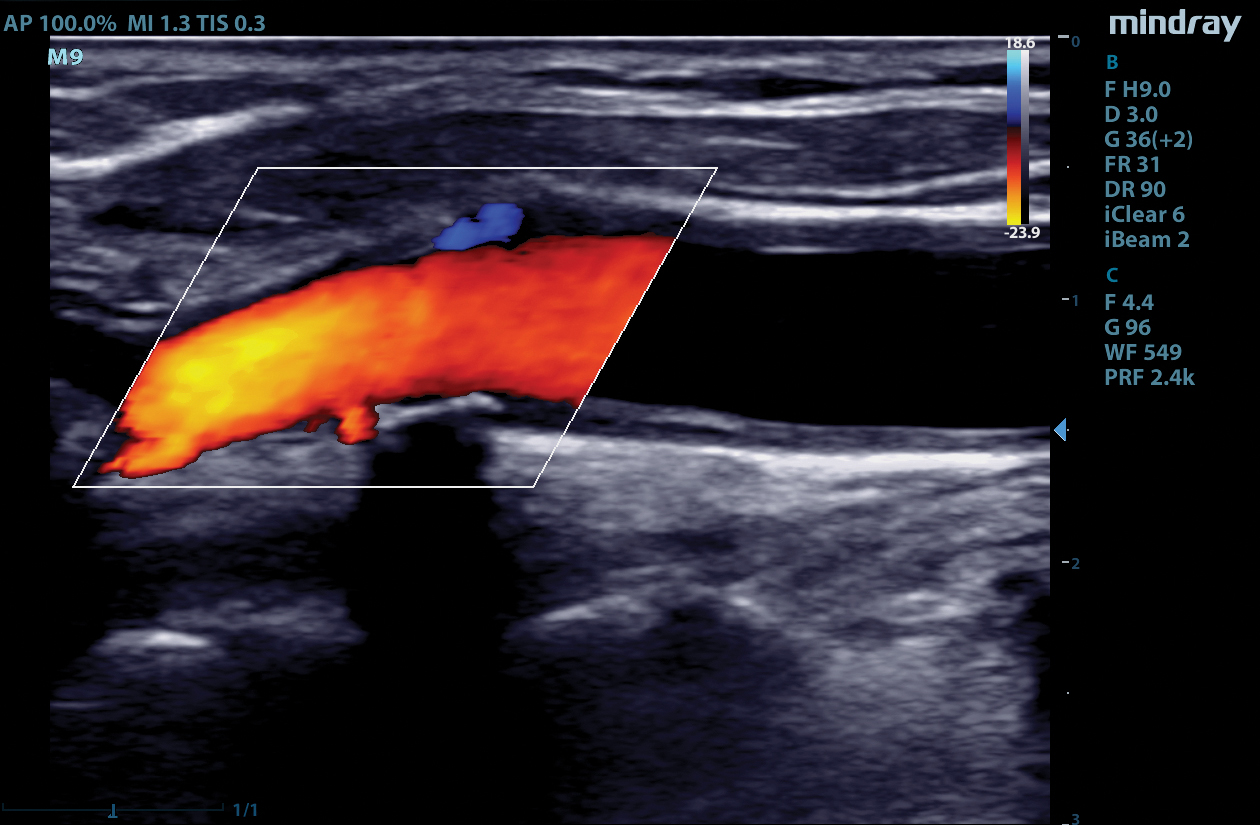

The M9 Ultrasound System Ruby Edition offers a fully-featured, compact ultrasound solution for your most challenging point-of-care exams. Delivering image clarity and advanced capabilities previously only available on larger, cart-based systems, the M9 System defines the new standard for intelligent performance in a mobile, laptop design.

Equipped with single crystal transducers and 3T™ technology for a wide range of exams, the M9 System is a versatile platform for advanced imaging in the vascular lab, emergency departments, critical care environments, and anesthesia practices. The System’s slim profile and ergonomic design allow for effortless flexibility and mobility. Whether it be ultrasound guided procedures at the patient’s bedside or transesophageal echocardiography (TEE) imaging in the critical care unit, this platform can do it all.